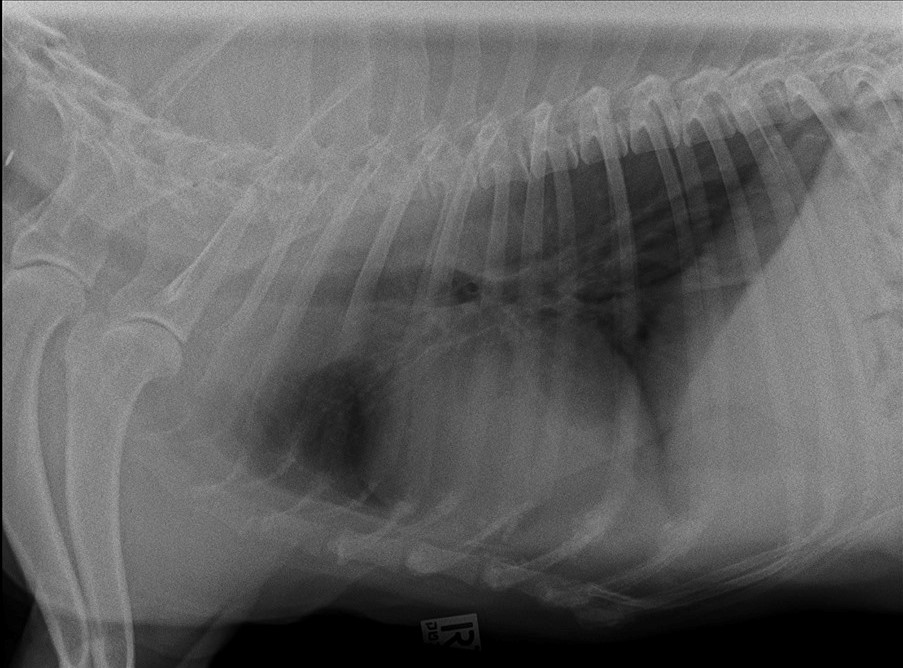

ואז קרה הבלתי יאמן! התחלנו לטפל במחלה הנדירה (מיאסטניה גרביס) והפלא ופלא סנופ החלים!!! בפעם הראשונה מזה שנה, הוא הפסיק להקיא ובצילום בית חזה שביצענו לו הוושט שלו היתה לראשונה תקינה לחלוטין.

בצילומים: סנופ (שייבדל לחיים ארוכים), צילום בית חזה בתקופת המחלה (הוושט המורחבת מסומנת באדום) וצילום בית חזה לאחר החלמה (בבית חזה תקין לא רואים את הוושט).